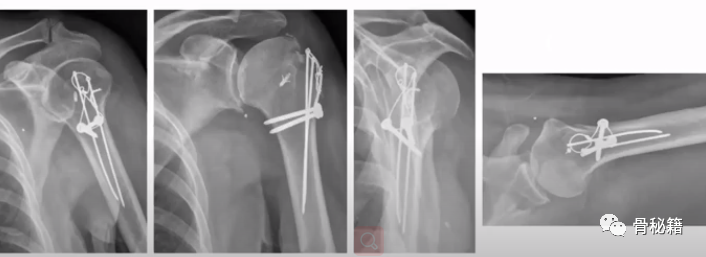

3、大结节骨折